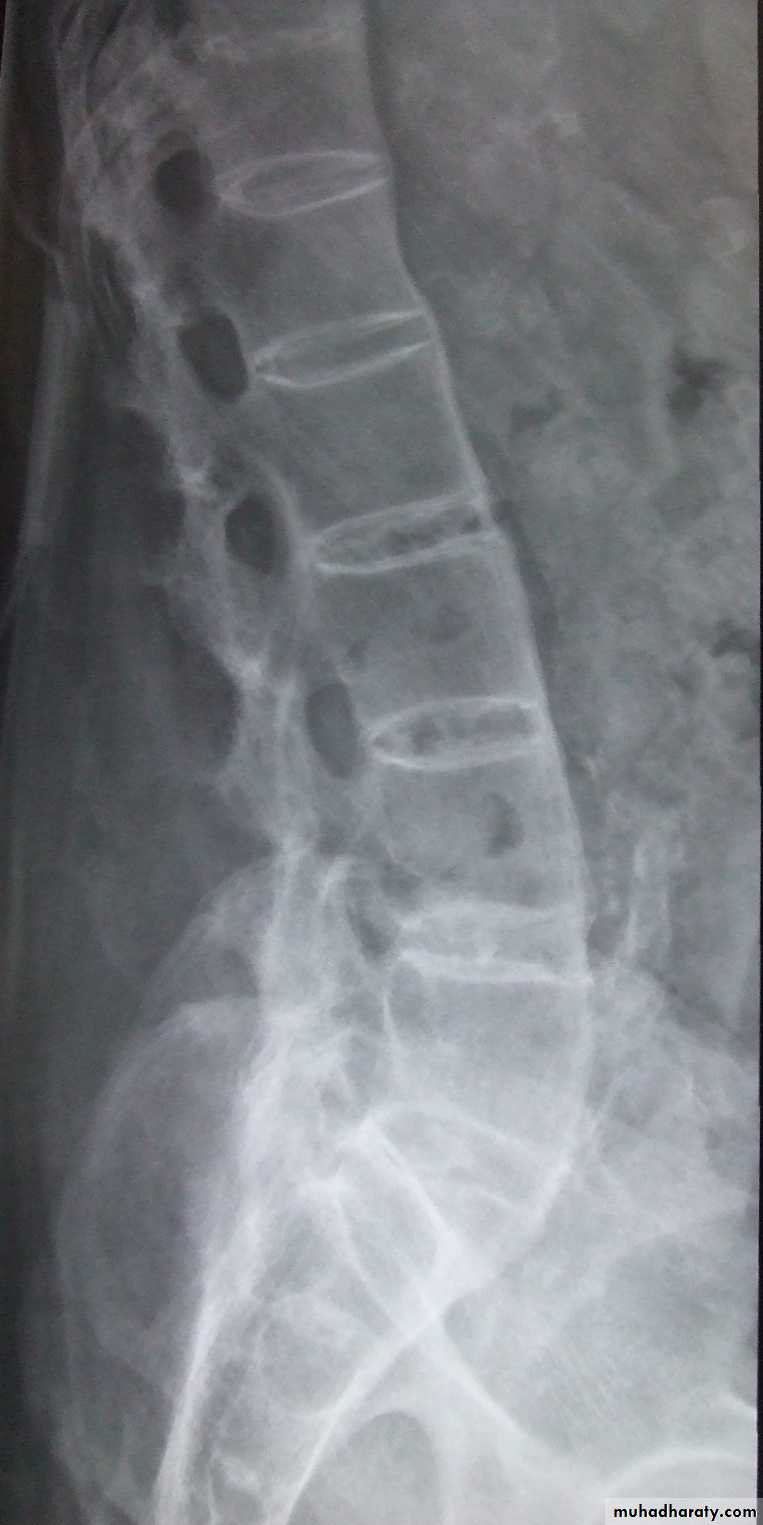

In the Spine :

* Lower cervical and low lumbar spine are most comonly affected.* Osteophytes may encroach on neural foramina (best seen on oblique views).

*Vacuum phenomenon: gas (N2),is pathognomonic of the degenerative process.

* OA of the spine occurs in the apophyseal joints .

* Degenerative spondylolisthesis (pseudospondylolithesis)

Lumbar spondylosis. There is distal narrowing and a vacuum

phenomenon is present in the degenerative discs. Marginal osteophytes arepresent. Inferiorly the facet joints show features of degeneration and, with the increase in lordosis, the spinous processes are in contact

• Scheuermann's disease : (adolecent Kyphosis).

• osteochodrosis of the vertebral end plates .• Usually affects 8- 10 years , characterized by erosion of anterior superior and inferior vertebral margin resulting in decrease in the height of anterior part of the vertebra (vertebral wedging ) ending with kyphosis.